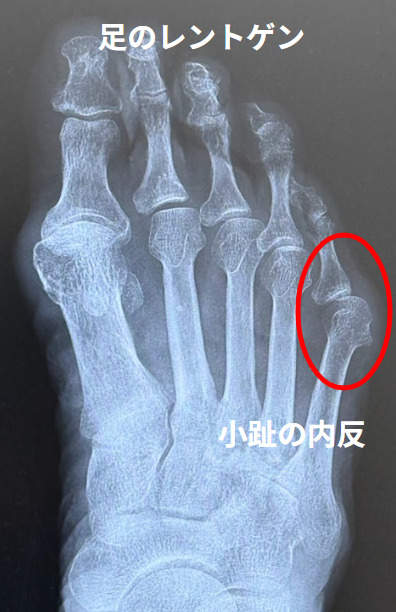

内反小趾(Bunionette)

内反小趾(Tailor’s Bunion, Bunionette)とは

足の小指(第5趾)がMTP関節で母趾側に曲がる疾患です。バニオネット(bunionette)、もしくは「Tailr’s bunion」=仕立て屋の外反母趾と言われます。「足の小指の骨の異常」と考えるとわかりやすいでしょう。

内反小趾の検査

内反小趾の進行状態を確認するために、足のX線検査を行います。足趾の変形の程度と偏平足の合併を評価します。内反小趾角は14°以内、M4/5角は8°以内が正常です。